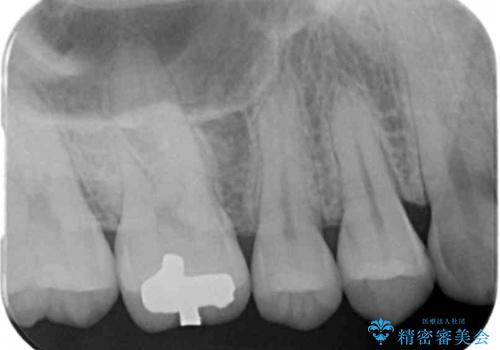

- 銀歯を白くしたいとのことで来院されました。

セラミックインレーでの治療をしていきます。

- 右上6 セラミックインレー 77,000円×1本費用は治療当時の料金となります

銀歯をセラミックにやり替えることで審美性を改善することができます。

適合の良いセラミックインレーを装着することで、今後の虫歯発生リスクを抑えることができます。